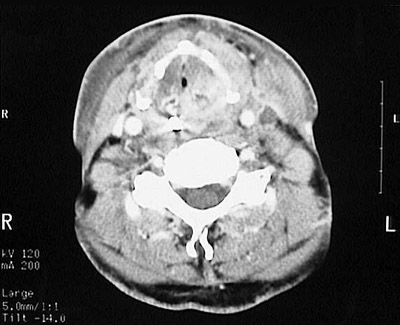

This head CT scan demonstrates an ill-defined infiltrative mass of the thyroid, nearly obliterating the trachea, consistent with an anaplastic carcinoma.